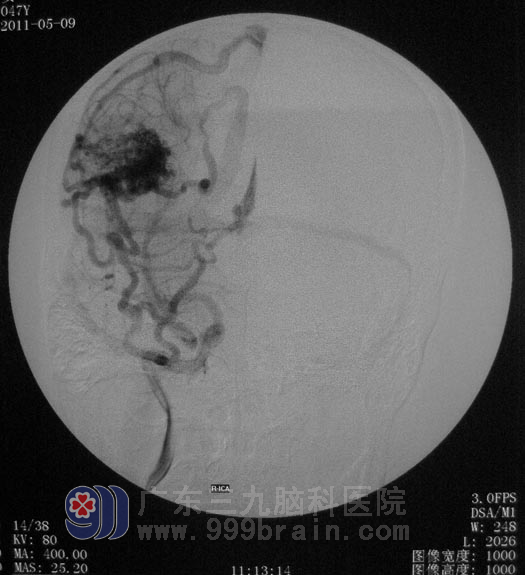

行全脑血管造影检查,结果显示:右颞枕动静脉畸形,约3cm×4cm大小,畸形血管团有三条动脉供血,主要为右侧大脑中动脉分支的供血。经过反复讨论及仔细地斟酌,鲁明主任为杨老师制定下治疗方案:先行部分畸形血管栓塞,再根据栓塞后情况行开颅切除没有完全栓塞的畸形血管。

▲栓塞前